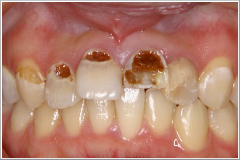

正月気分間覚めやらぬ1月8日、「前歯が折れてしまって、成人式に出られないんです。何とかならないでしょうか?」 という電話がありました。晴れの舞台に“歯っ欠け”ではさすがに気の毒で、「仮歯くらいなら、なんとかなりますよ」と答え、来院してもらうことになりました。その患者さんは20歳の女性(Cさん)で、左の写真の様なお口の状態でした。